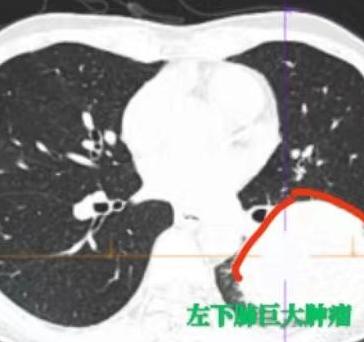

查出局部晚期肺癌,一开始被告知已经没法手术了……谁能想到,几个月之后复查,肺上的肿瘤竟然几乎消失了!从“不能手术”到“肿瘤明显缩小、成功手术”,他们到底经历了什么? 最近我做了4台肺癌手术,其中有3台都是经过“新辅助治疗”之后,才争取到手术机会的。 这几位患者中,有2位是先做了“新辅助免疫+化疗”,1位是做了“新辅助靶向治疗”。 很多朋友可能听说过靶向治疗——先做基因检测,如果有突变,配上合适的靶向药,吃下去效果往往很明显。但如果没有相应突变,可能就要考虑“免疫治疗+化疗”这个组合拳。 免疫治疗现在技术已经比较成熟,其实就像我们平常打点滴一样,输的是一种抗体(PD-1 或 PDL-1抑制剂)。 它的作用,简单说就是:帮我们的免疫系统“认出”癌细胞——因为癌细胞会伪装自己,躲避免疫系统的攻击,而免疫药物可以撕掉这层伪装,让免疫细胞重新识别并消灭肿瘤。 这3位患者在经过药物治疗后,虽然肿瘤明显缩小了,但由于淋巴结之前有粘连、局部有疤痕,手术其实仍然非常难做。 好在最后都顺利切掉了病灶。更令人欣慰的是,病理结果回来显示:切下来的组织里已经找不到活的肿瘤细胞了。 这也给很多晚期肺癌患者带来了新希望,即使一开始不能手术,通过有效的药物治疗,也有机会达到手术条件,甚至实现临床治愈。[玫瑰][谢谢]